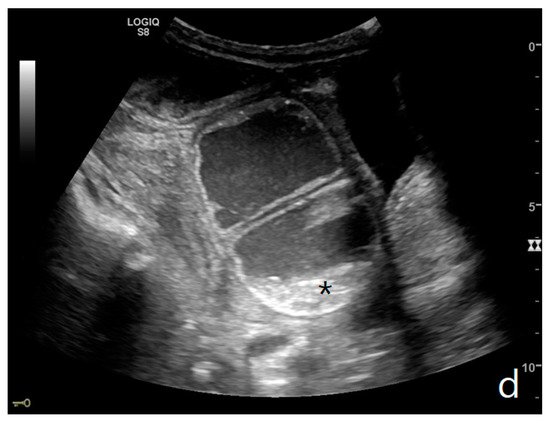

Parietal changes are characterized by the presence or absence of parietal and valvulae conniventes thickening and parietal wall stratification. The evaluation of parietal changes follows a dichotomic diagnostic process based on the reference values (normal thickness 1–3 mm, wall thickening >3 mm, thinned walls <1 mm): thickened walls/valvulae conniventes (YES/NO) or thinned walls (YES/NO) [11][12][3]. Although ultrasound allows us to identify the five concentric layers of the intestinal loops, this evaluation is not applied in the diagnosis of SBO. In practice, the evaluation is limited to the presence or absence of parietal stratification (two-layer double halo sign or three-layer target sign) (Figure 4a–d and Figure 5a,b) [11][3][13].

Figure 4. A complicated SBO in a 69-year-old male with gastric cancer and peritoneal carcinosis. Ultrasound images show long (a) and axial (b) evaluations of a fluid-filled, dilated small bowel loop with hyperechogenic floating material (shown with an asterisk) (b,d). Bowel peristalsis was absent. Mild parietal and valvulae conniventes thickening are present (c,d). Downstream loops present normal caliber (bowel jump diameter). Free fluid is interposed between bowel loops (black arrow) (b).

The valvulae conniventes (Kerckring valves, circular folds) are permanent folds composed of mucosa and submucosa that project into the intestinal lumen and are clearly visible in the case of fluid distension (keyboard sign) [5]. At an early stage of SBO, it is not uncommon to see the valvulae in the upstream loop appearing more numerous and closer to each other. As the occlusive state continues, the loop upstream of the obstructive fulcrum becomes weaker, bowel walls appear thin, and the folds flatte. The upstream loops more distant from the obstructive fulcrum may still present peristalsis, albeit reduced and ineffective. In complicated ileus, with the onset of vascular loop distress, the walls and valvulae become thicker and weaker due to parietal edema and venous stasis, with possible dramatic parietal necrosis and subsequent perforation (Figure 4a–d and Figure 5a,b) [2][14].